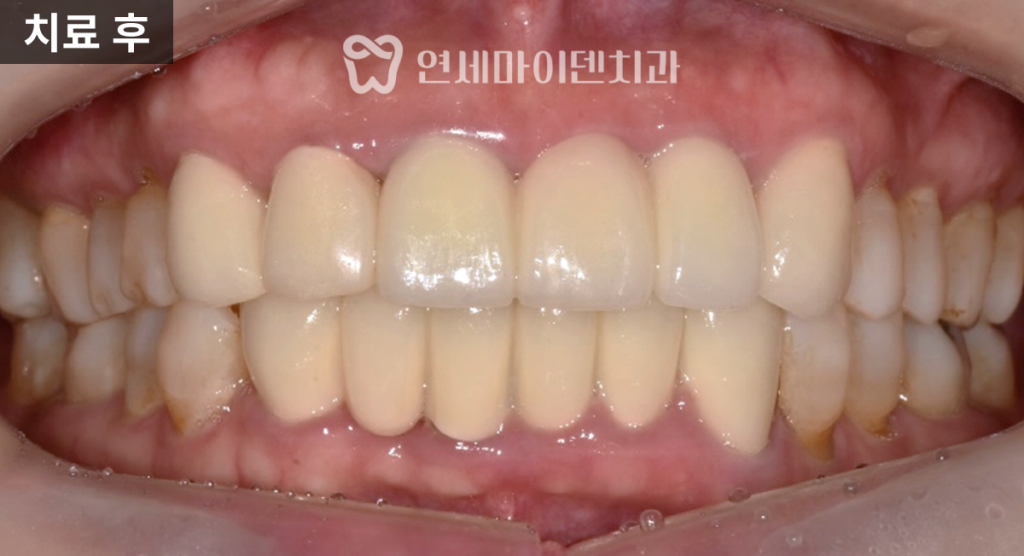

임플란트로 치료한 앞니는

안정적으로 자리 잡았고,신경치료를 시행한 치아는

치근단 낭성 병변이

자연스럽게 치유되면서

추가적인 치근단 수술 없이

회복을 확인할 수 있었습니다.

최종 보철을 통해

기능과 심미성을 모두 회복했으며,해당 케이스는

치료 후 3년이 지난 현재까지도

안정적으로 유지되고 있습니다.